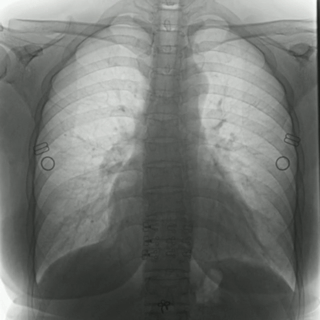

不同于常規(guī)DR只能進(jìn)行平片攝影檢查,普利德多功能動(dòng)態(tài)平板DRF動(dòng)靜兼?zhèn)?,可?shí)現(xiàn)大幅面低劑量透視檢查,在日常的體檢工作中,比如胸部及肺部檢查,可對(duì)重疊部位病變進(jìn)行可視化觀察及多角度旋轉(zhuǎn)體位,發(fā)現(xiàn)疑似病灶可瞬時(shí)完成高清點(diǎn)片,顯著提高診斷的準(zhǔn)確性。

動(dòng)態(tài)采集幀率最高可達(dá)30幀/s,影像細(xì)膩流暢,便于醫(yī)生對(duì)細(xì)微病變的觀察。17×17英寸大幅面成像,在透視過程中能對(duì)患者的胸部腹部等部位實(shí)現(xiàn)大范圍覆蓋,便于從整體上觀察組織信息,更加全面且精準(zhǔn)的捕捉病灶。